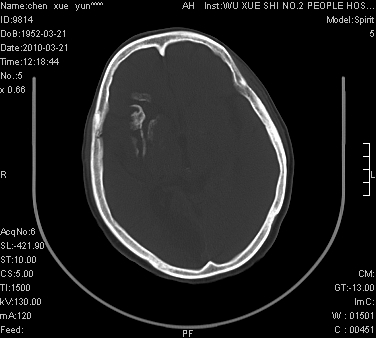

性别:不详;年龄:58岁;病史:不详。

ct表现:1、右侧额颞叶深部不规则钙化密度团块,呈弯曲条带状,占位效应不明显,考虑少枝胶质细胞瘤可能性大于血管瘤。2、右枕叶大片不规则低密度影,密度近似于脑脊液,右侧侧脑室后角及三角区扩张,考虑为陈旧性脑梗塞。

讨论:1、这个病灶的钙化有点像脑回样钙化,因此我最初考虑颅面血管瘤病(sturge-weber综合征),但是查阅了我们网站上的几个颅面血管瘤病病例,钙化均位于脑实质表面,沿脑回分布,而这例病灶位置较深,因此可以否定“颅面血管瘤病”这个诊断。

2、卜一会员曾经说过:少枝胶质细胞瘤的典型征象为弯曲条带状钙化,可作为定性的可靠征象(http://www.radida.com/news_view.asp?id=5150)

3、血管瘤也可以出现弯曲条带状钙化,但血管瘤多数出现“负占位”效应,即病灶周围的脑室、脑池及脑沟不是受压变窄,而是局限性的增宽。